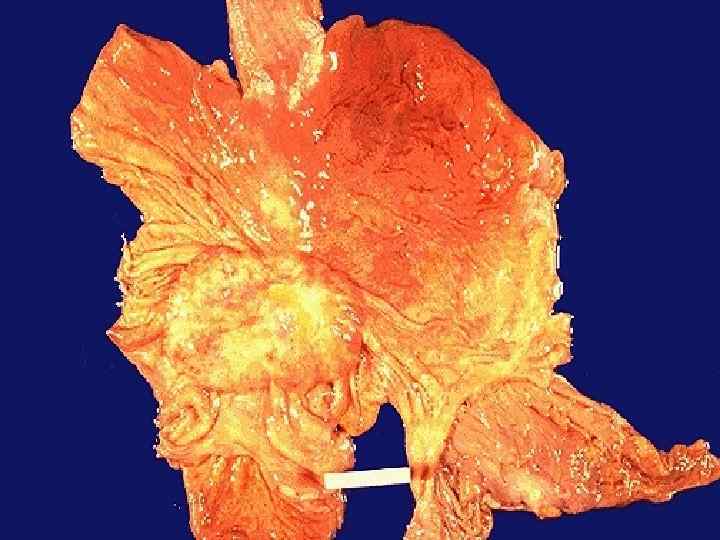

Синдром фон Восс-Черствого M. Urioste Azcorra, P. Aparicio Lozano. Sindrome de von Voss-Cherstvoy (DK-Focomelia): Primera descripciуn en Espaсa y revisiуn de la literature // An Esp Pediatr 1997; 46: 299 -302.